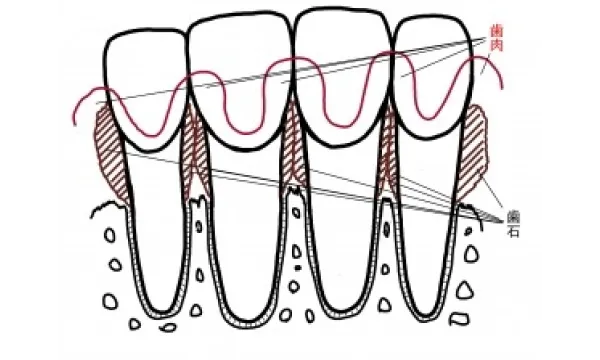

歯周病になると

骨は歯肉の中で吸収し、歯肉の中と外には歯石と歯垢がこびりつき、それに伴い歯肉は腫れあがっています。 この状態に対し、患者さんのブラッシングが解消、歯科医院側では歯石取りとみがき残した部分のクリーニング、場合によっては手術を行って磨きやすい環境に変えてそれを持続すると…。

歯周病の初期の段階は歯肉炎と言います。歯肉炎では、歯周病菌が歯と歯肉の間に入り込み、プラークや歯石がたまりはじめます。 歯肉炎が進むと、歯と歯肉の間に歯周ポケットができて歯周ポケットにプラークや歯石がたまってきます。この状態を放置すると、歯周ポケットが深くなり、歯肉が腫れたり、出血するようになります。 そして、さらに歯周病が進行すると、歯槽骨が溶けはじめ、歯が支えられなくなります。最終的には歯が抜けてしまうことになります。皆様の大切な歯を守るためには、初期の段階から治療や正しいケアが必要です。